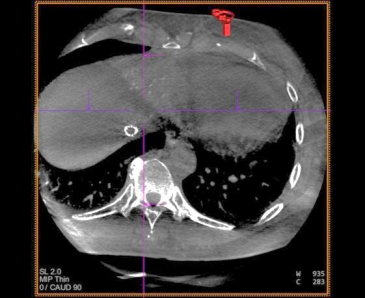

患者仰卧,右侧腹股沟区消毒铺巾,穿刺右股动脉,置入5.0Fr 导管鞘,经鞘进入 RH 导 管,在主动脉弓处成形,选择性进入腹腔干,行血管造影,肝右叶无明显肿瘤染色,肝左动 脉由胃左动脉发出,采用科睿驰医疗提供“智鹏”2.0Fr 微导管选择进入肝左动脉造影,行CBCT 扫描可见肝左内叶肿瘤强化病灶,大小约 1cm,肝左外叶病灶与胃左动脉分支共干,无法避开进一步超选择,超选择进入肝左内叶,造影明确到达把血管,选用 100-300μm“睿 渊”DiaSphere®载药微球加载 50mg 表柔比星,载药完毕后,予注入 2ml 载药微球,再 次行 CBCT 扫描,原肝左内叶病灶无强化,术中患者生命体征平稳,撤出导管,压迫止血、 包扎,患者安返病房。

术中 CBCT 可见肝左内叶肿瘤强化病灶

栓塞结束后 CBCT 扫描,原肝左内叶病灶无强化